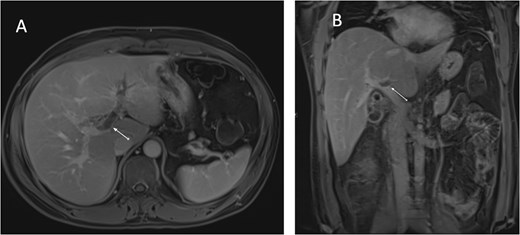

An ultrasound of the abdomen showed an impacted stone at the neck of the gallbladder with acute cholecystitis. The patient was admitted and started on IV antibiotics. He developed tachycardia reaching 110 bpm and had a high white blood cell count; therefore, the decision was made to proceed with a contrast-enhanced computed tomography (CT) scan, which showed evidence of acute cholecystitis and left PVT (Fig. 1). The medical team was consulted, and IV heparin without bolus was started. The gastroenterology team was consulted for his high bilirubin levels and advised for magnetic resonance cholangiopancreatography (MRCP), which was done the next day and confirmed the findings of left PVT (Fig. 2). MRCP also showed a micro perforation of the gallbladder and no biliary obstruction or stones (Fig. 3).

Axial cut MRCP showing T2-weighted images. Arrow indicates area of micro-perforation and small collection.